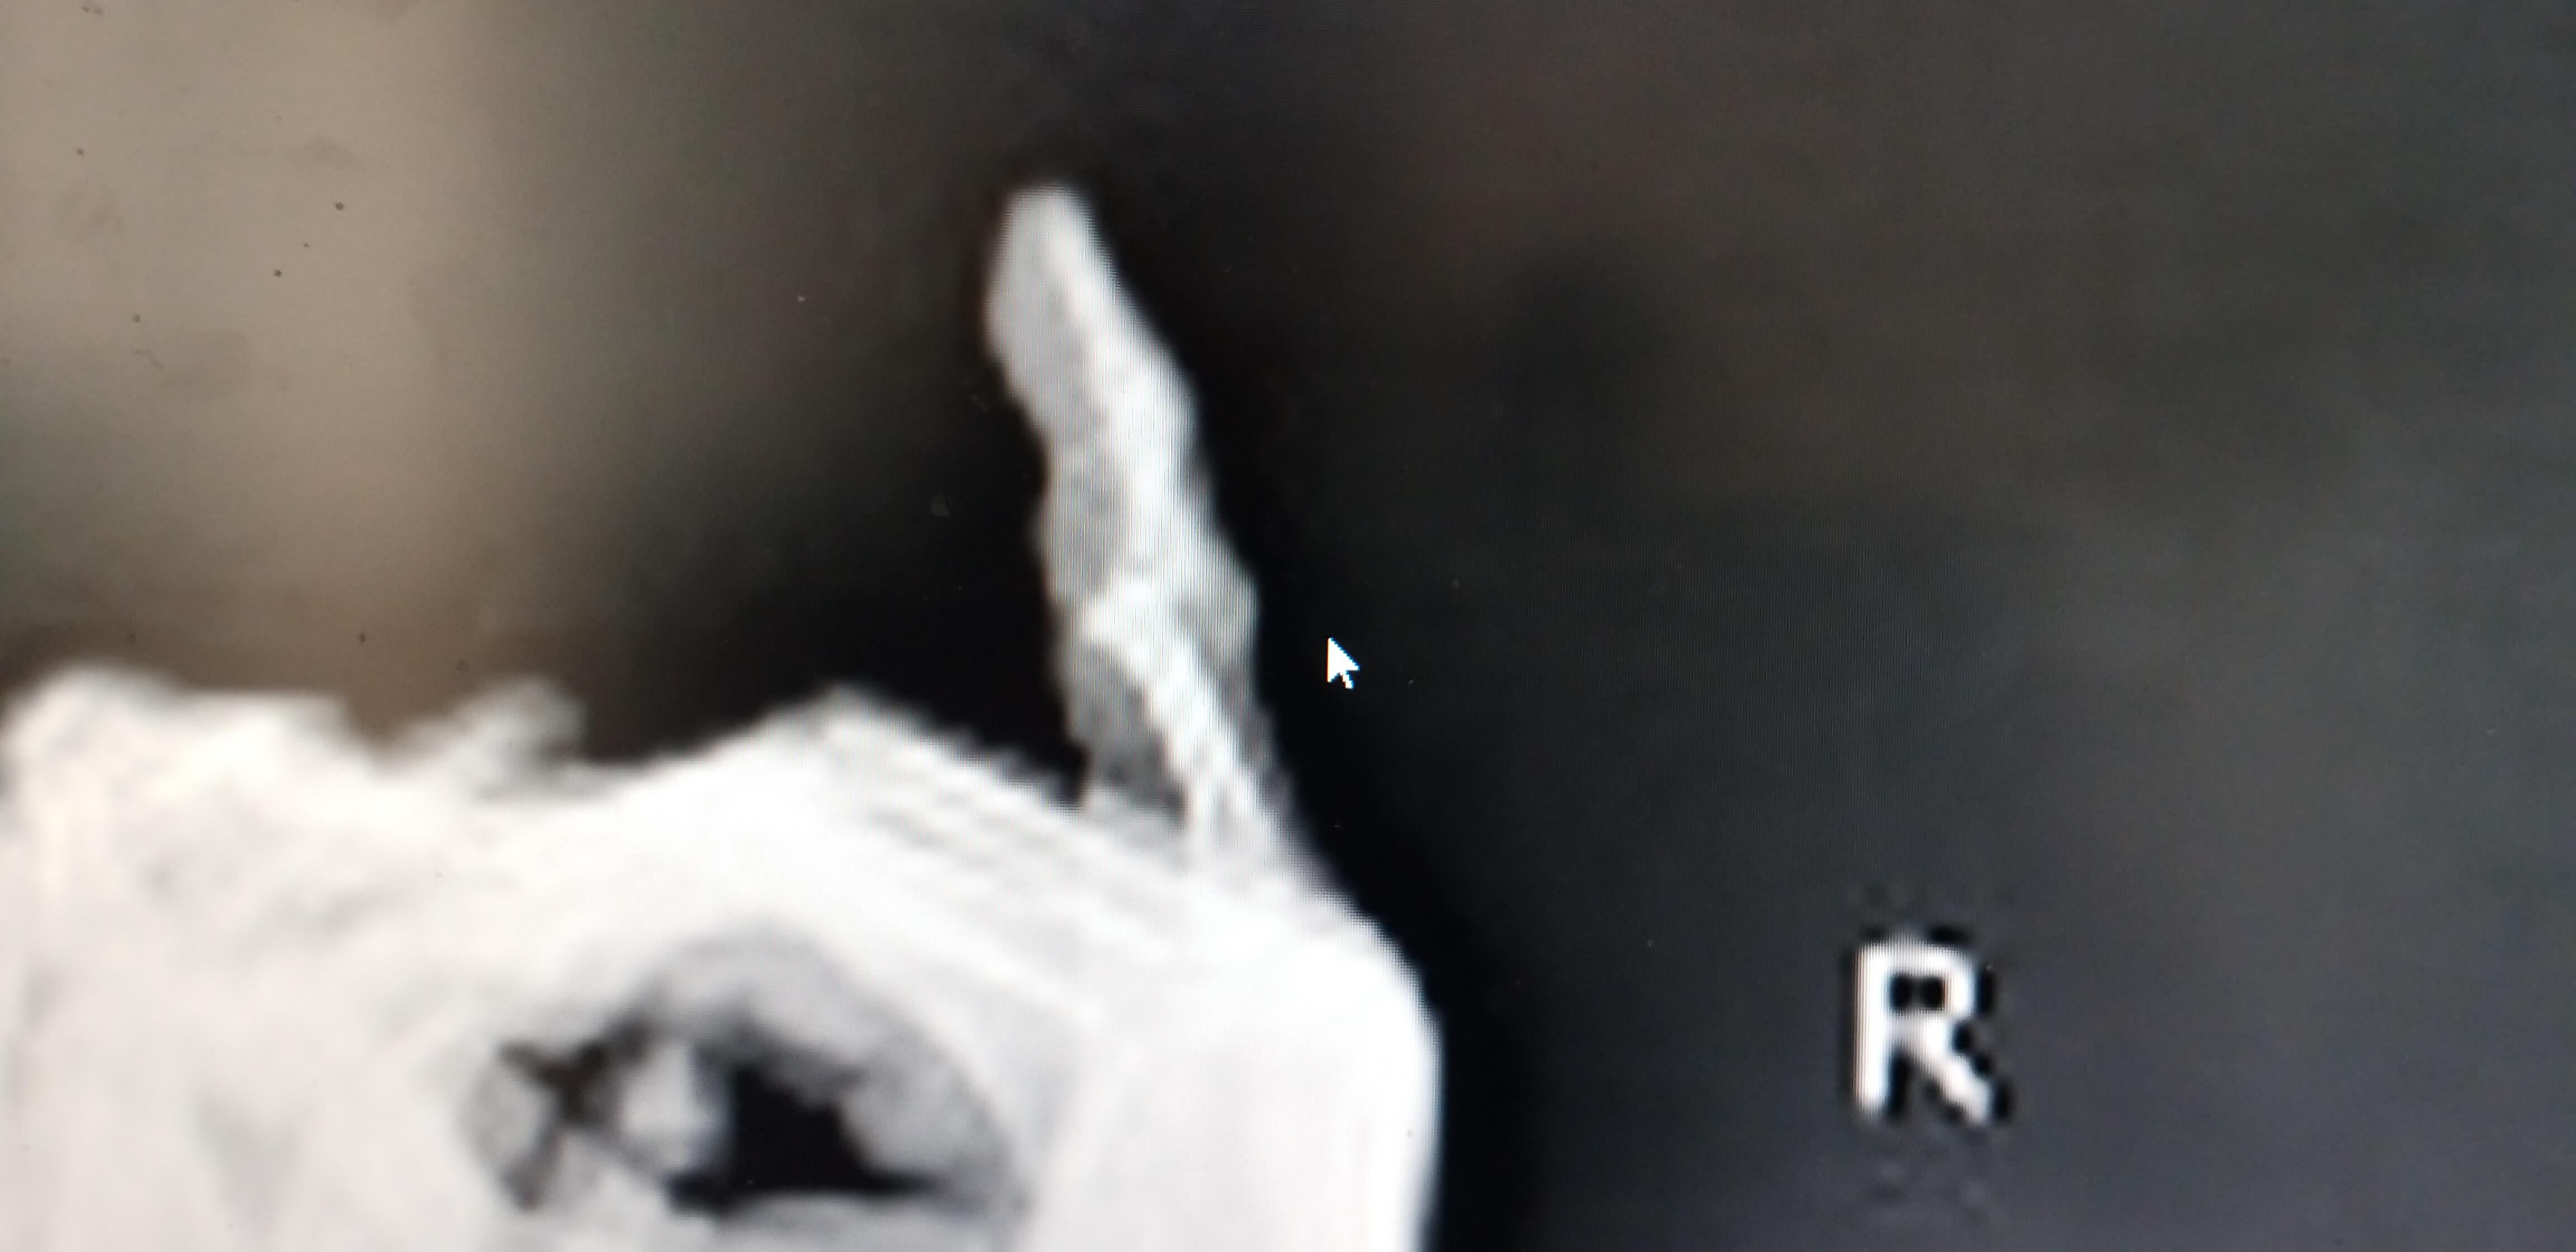

의사선생님 말씀으로는 인대가 완전 파열된 상태이며 인대가 원래 뼈에 붙어있는 상태에서 충격이나 골절로 파열될때 뼈조각이 같이 떨어지는 경우가있다고 하셨고 나의 상태도 손가락 인대 완전 파열과 뼈조각 제거 수술을 바로 진행해야 된다는 진단을 받았습니다.

뼈조각은 크기나 형태에 따라 문제가 발생되지 않아보이고 새끼손가락의 배열도 잘맞아서 수술은 권유하지 않았습니다.